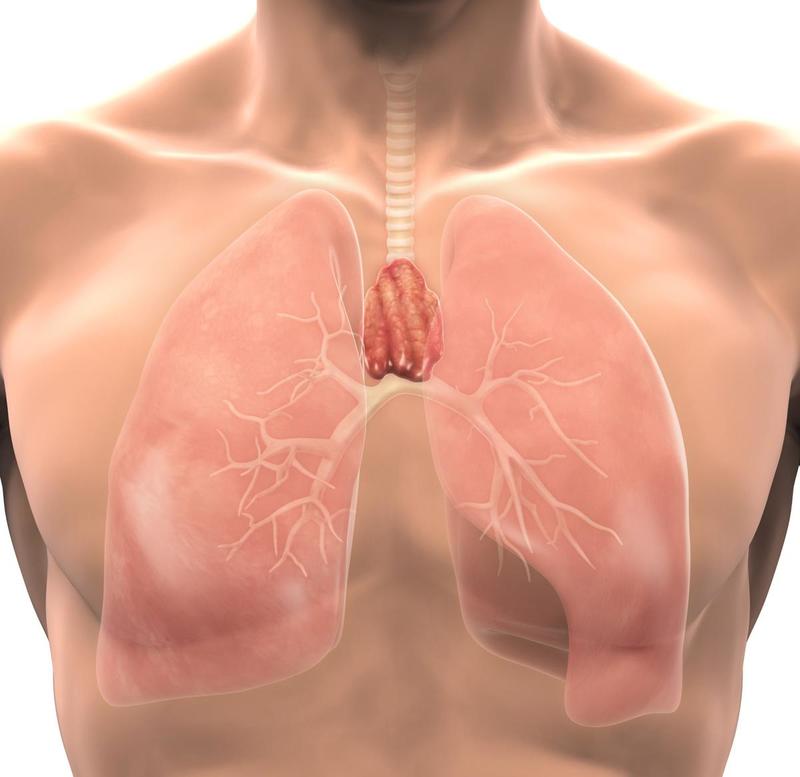

Фотографии вилочковой железы тимуса: структура и функции